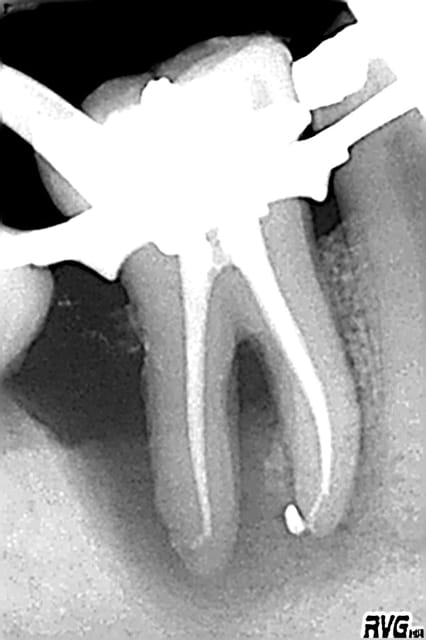

une 46:le pronostic?

35:decouverte fortuite sous un si joli inlay or que je l'ai rescellé(adieu CCC...)

et un puff:sniff!(j'essaye pourtant,stephane,j'essaye de les supprimer)

Effectivementm, la 46, pas sur qu'e;;e est le temps de cicatriser. Mais, l'echec sera d'origine paro non endodontique.

un excellent exemple de lesion endo paro. Traitement paro prevu ?